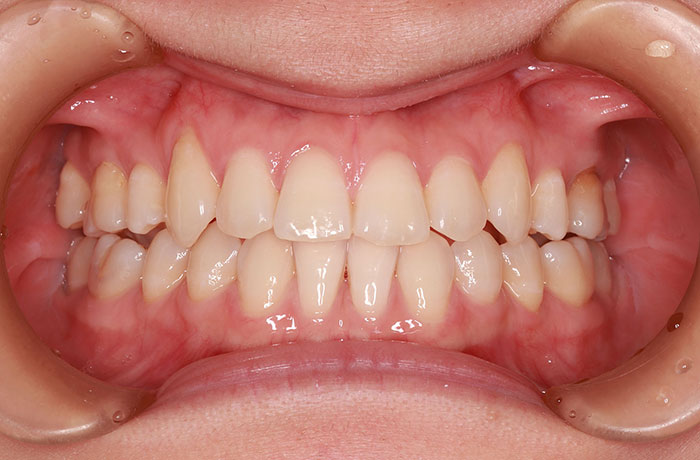

after

年齢 28歳

性別 女性

治療名称 唇側ブラケット装置(ワイヤー矯正)

総額治療費用 880,000円(税込10%) 金額備考 精密検査料・診断料 33,000円(税込10%)

治療期間 2年6か月 通院頻度など 1か月ごと

治療内容

患者の症状 叢生、上下顎前突

治療方法 上下顎小臼歯の4本抜歯して唇側マルチブラケット装置にて矯正

治療結果 叢生の解消、口元の突出感も緩和され咬み合わせが良くなりました。

※治療結果は患者様によって個人差があります。

その他治療に関する情報 装置撤去までの通院回数は23回、その後の保定期間(2年間)は3か月に1度の通院。

治療を行う上での注意点

リスク/副作用 治療前に親知らずの抜歯が必要な場合があります。